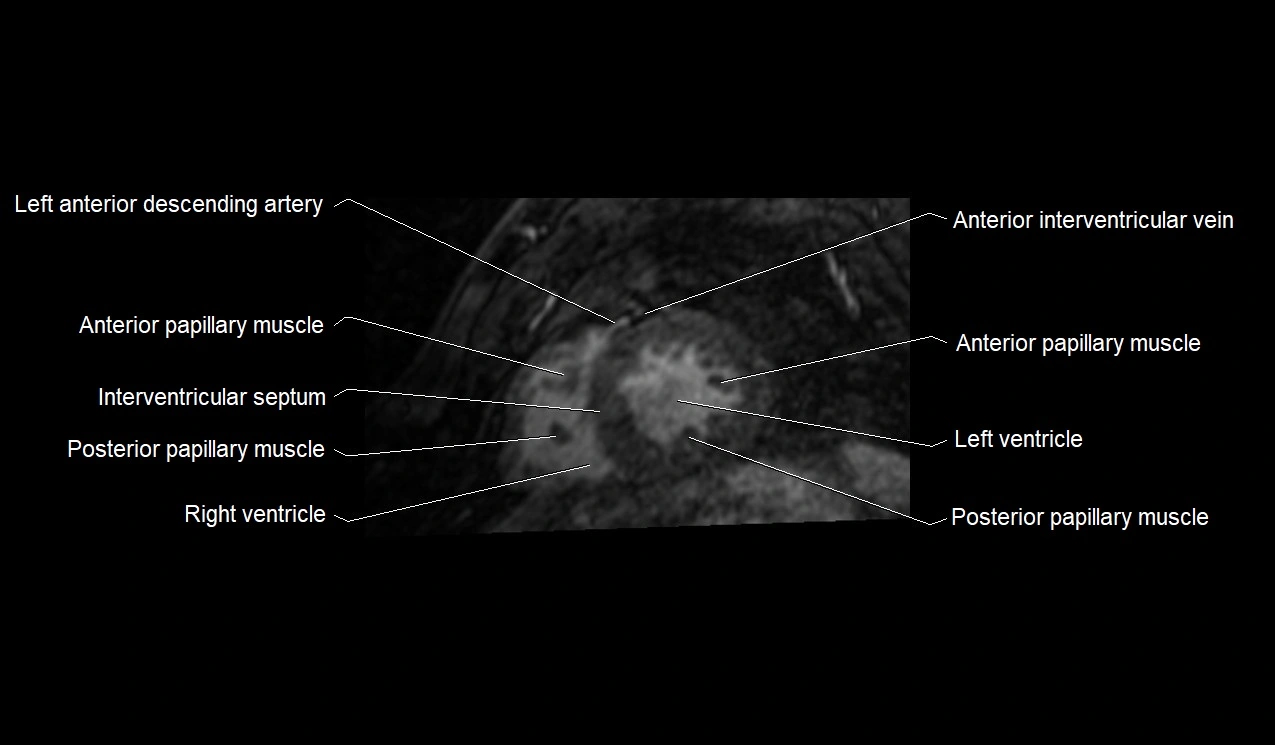

MRI image